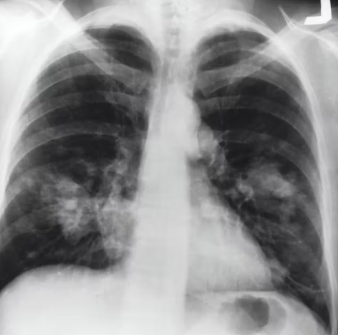

천식을 제대로 관리하지 않거나 치료가 늦어질 경우 다양한 합병증이 발생할 수 있습니다. 주요 합병증으로는 심한 천식 발작(생명 위협), 폐렴, 기관지 비가역적 변화(폐기능 저하), 호흡 부전, 폐성 심장병, 우울증, 불안 장애 등이 있습니다.

또한, 장기적인 스테로이드 사용으로 인한 골다공증, 백내장, 녹내장 등의 부작용도 발생할 수 있습니다. 이러한 합병증들은 삶의 질을 심각하게 저하시키므로, 철저한 관리를 통해 예방하는 것이 무엇보다 중요합니다.

합병증을 예방하기 위해서는 약물 치료를 꾸준히 유지하고 천식 유발 요인에 대한 노출을 최소화하는 것이 필수입니다. 정확한 흡입기 사용법을 익히고, 인플루엔자 및 폐렴구균 백신 접종을 통해 호흡기 감염을 예방해야 합니다.

또한, 피크 플로우 미터(최대 호기 유량 측정기)를 이용하여 정기적으로 폐 기능을 측정하고, 자신만의 천식 관리 계획을 세워 급성 악화 시 즉시 대처할 수 있도록 준비해야 합니다. 동반된 알레르기 질환이나 역류성 식도염 등도 함께 관리해야 합니다.

천식은 만성적인 경과를 보이는 질환이므로, 꾸준한 모니터링과 정기 검진이 매우 중요합니다. 주기적으로 폐기능 검사, 혈액 검사, 알레르기 검사 등을 통해 폐 기능의 변화와 염증 상태를 확인해야 합니다.

또한, 증상 일기를 작성하여 기침, 숨 가쁨, 쌕쌕거림의 변화를 기록하고, 급성 악화 징후가 보이면 즉시 의료진과 상담해야 합니다. 정기 검진은 질병의 악화를 막고, 필요한 경우 치료법을 변경하거나 보강하여 천식을 효과적으로 관리하는 데 결정적인 역할을 합니다.